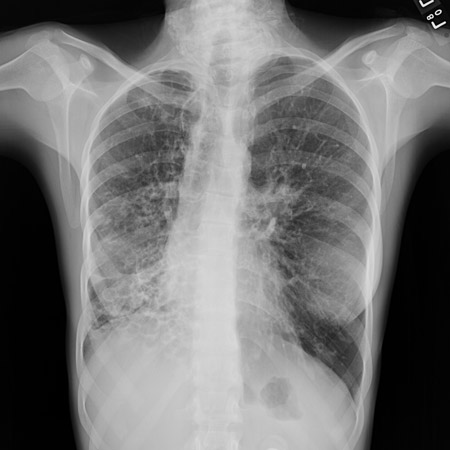

Uma radiografia torácica deve ser obtida no início da avaliação da tosse crônica.[38] Embora não seja diagnóstica das causas mais comuns, os achados podem facilmente desviar a avaliação para causas de maior gravidade como doenças pulmonares estruturais. Eles incluem câncer pulmonar, fibrose pulmonar, tuberculose, bronquiectasia, pneumonia, aspiração e sarcoidose.[Figure caption and citation for the preceding image starts]: Radiografia torácica mostrando hiperinsuflação em paciente com DPOC. A hiperinsuflação é causada pelo componente de enfisema na DPOC, em vez da bronquite crônica subjacente aos sintomas da tosseDo acervo pessoal do Dr. M. A. Sharifabadand, SUNY na Stony Brook School of Medicine, Departamento de Medicina Pulmonar e Intensiva, Mineola, Nova York, e Dr. J. P. Parsons, The Ohio State University Medical Center, Columbus; usado com permissão [Citation ends].

[Figure caption and citation for the preceding image starts]: Radiografia torácica mostrando adenopatia hilar bilateral em um paciente com sarcoidoseDo acervo pessoal do Dr. M.P. Muthiah, Divisão de Medicina Pulmonar e Intensiva e Medicina do Sono, Universidade do Tennessee [Citation ends].